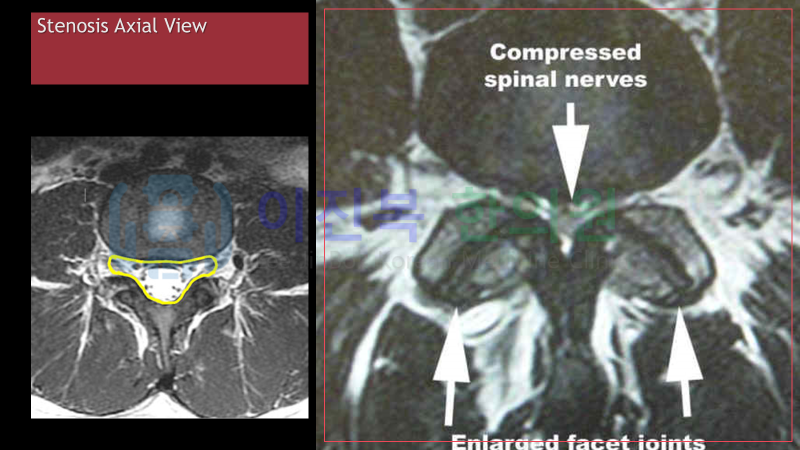

오늘은 척추관 협착증에 대해 알아보겠습니다.